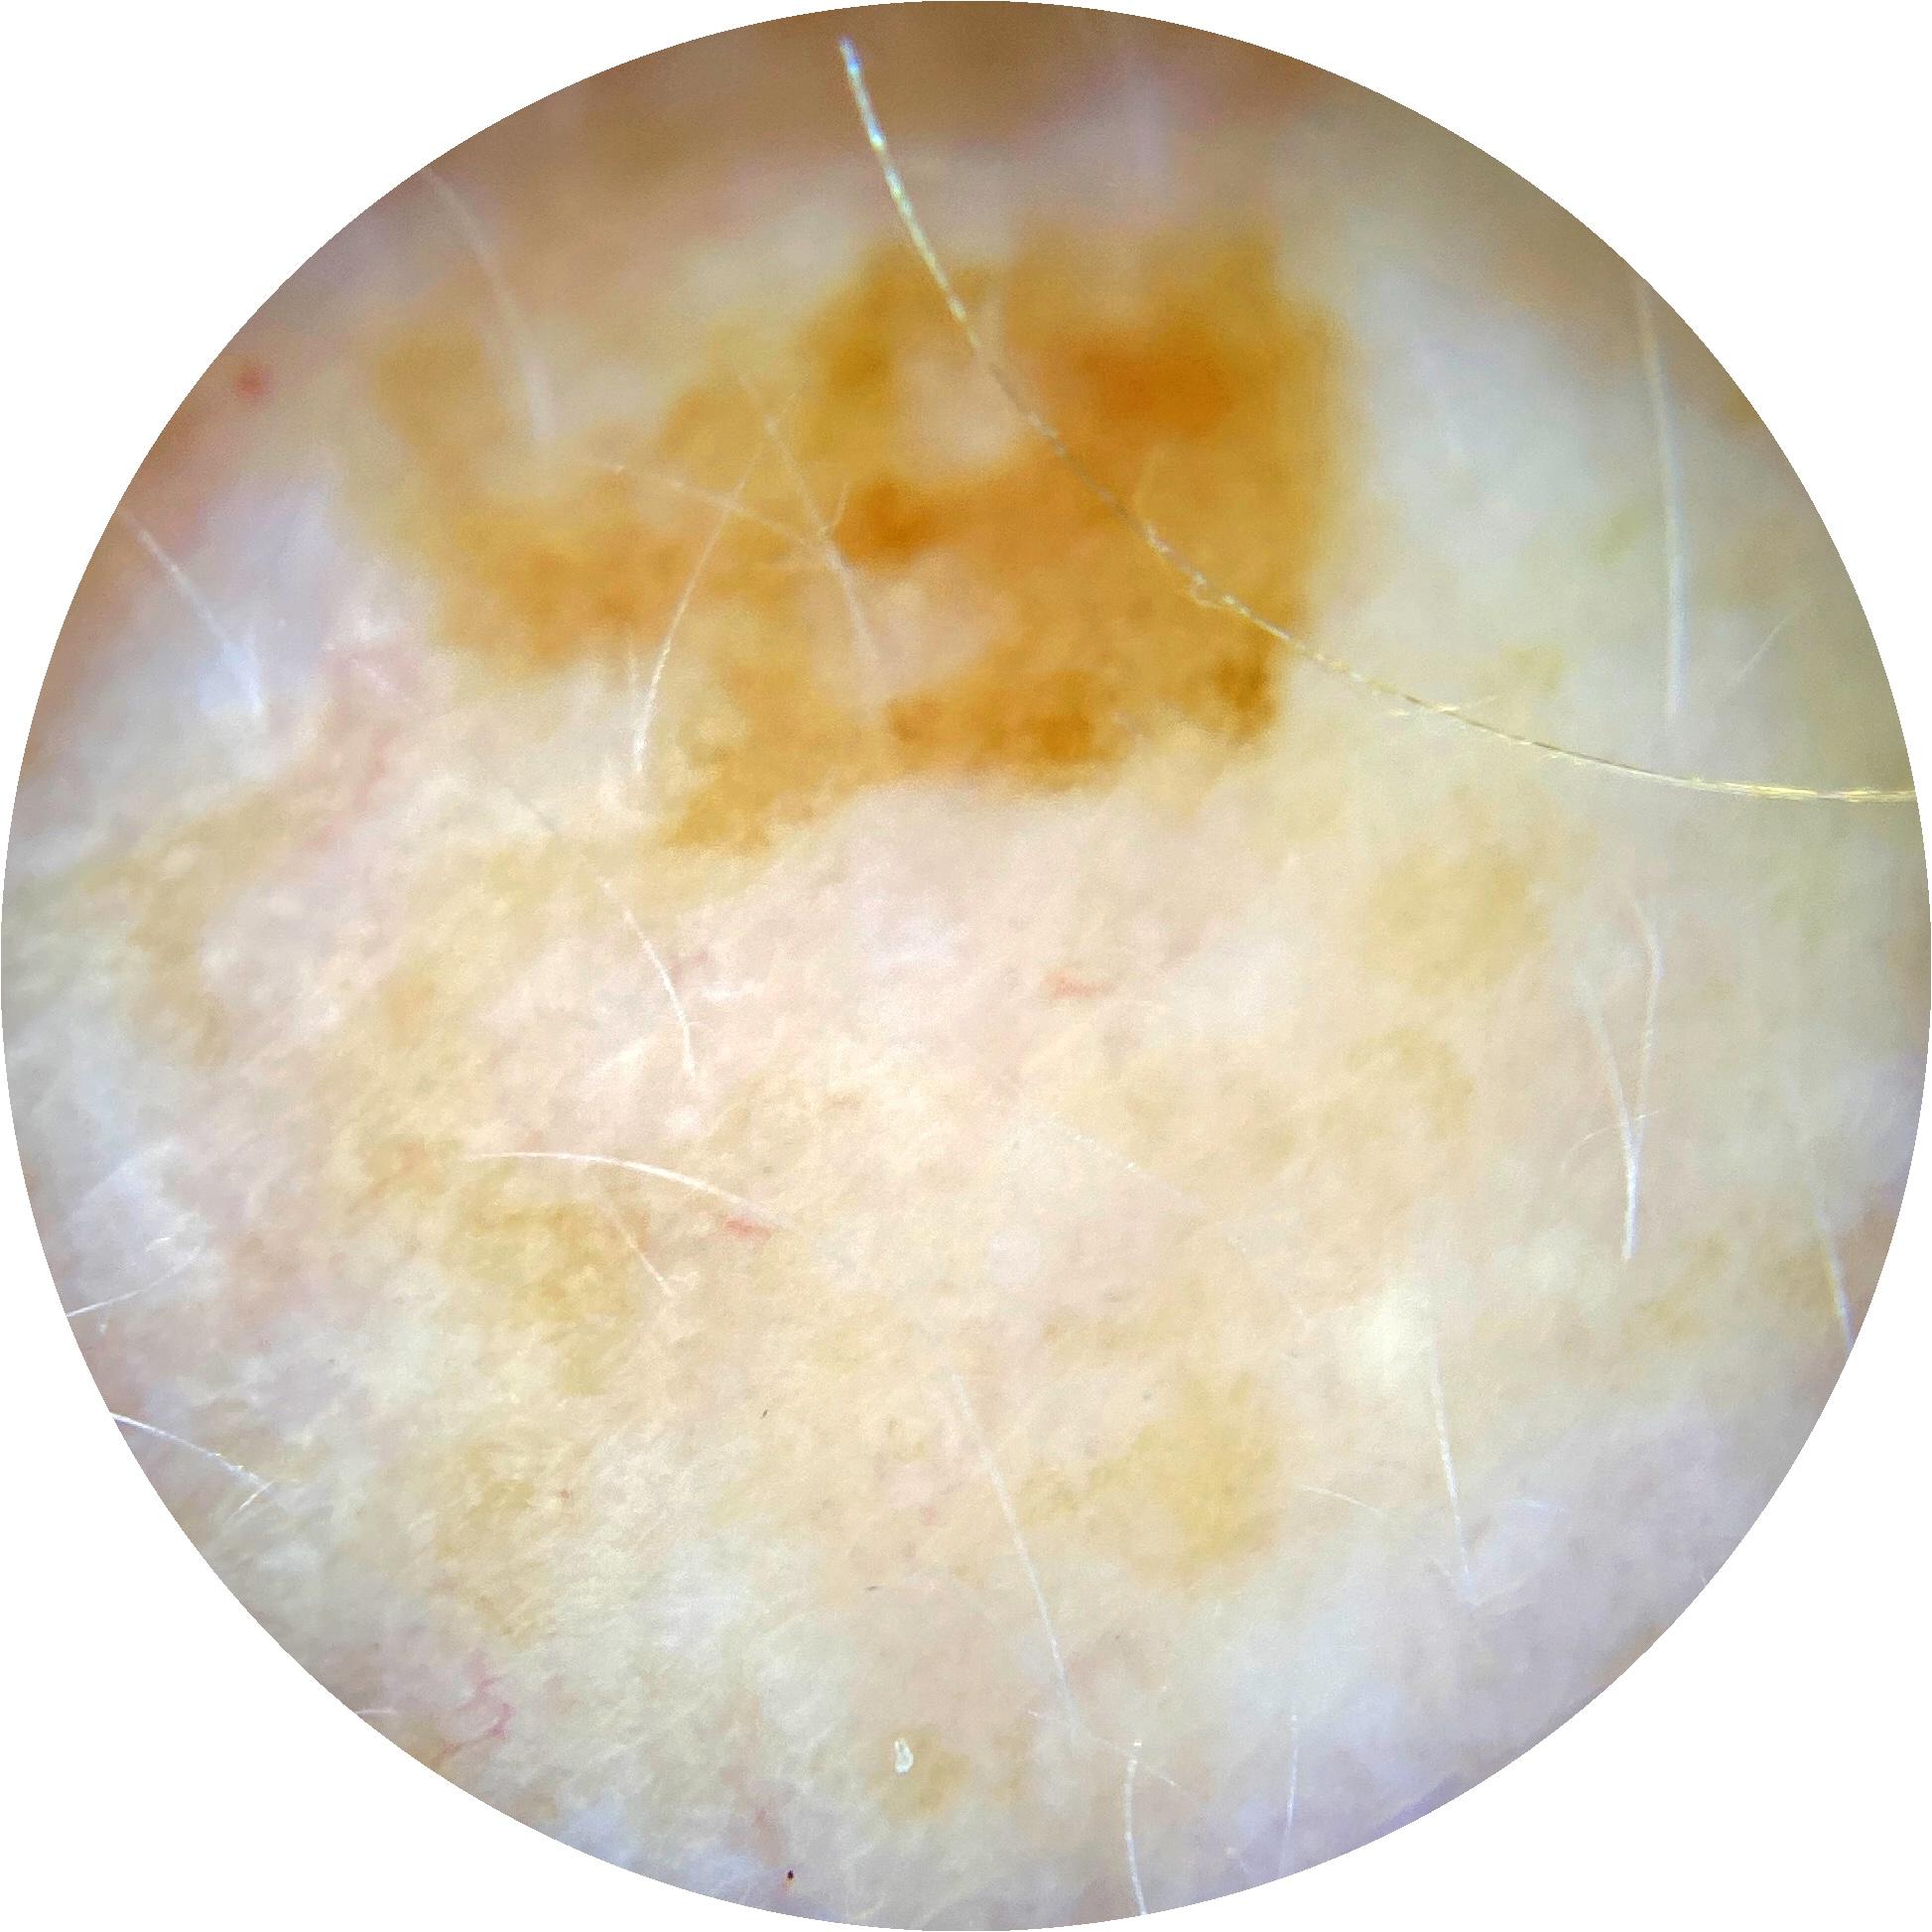

ISIC_7268078

Information

1781 x 1781

Clinical

Field Value

acquisition_day 226

age_approx 60

anatom_site_1 Trunk

anatom_site_2 Posterior trunk

anatom_site_general posterior torso

concomitant_biopsy False

diagnosis_1 Benign

diagnosis_confirm_type single image expert consensus

family_hx_mm False

image_manipulation instrument only

image_type dermoscopic

lesion_id IL_3039460

patient_id IP_4030734

personal_hx_mm True

sex female